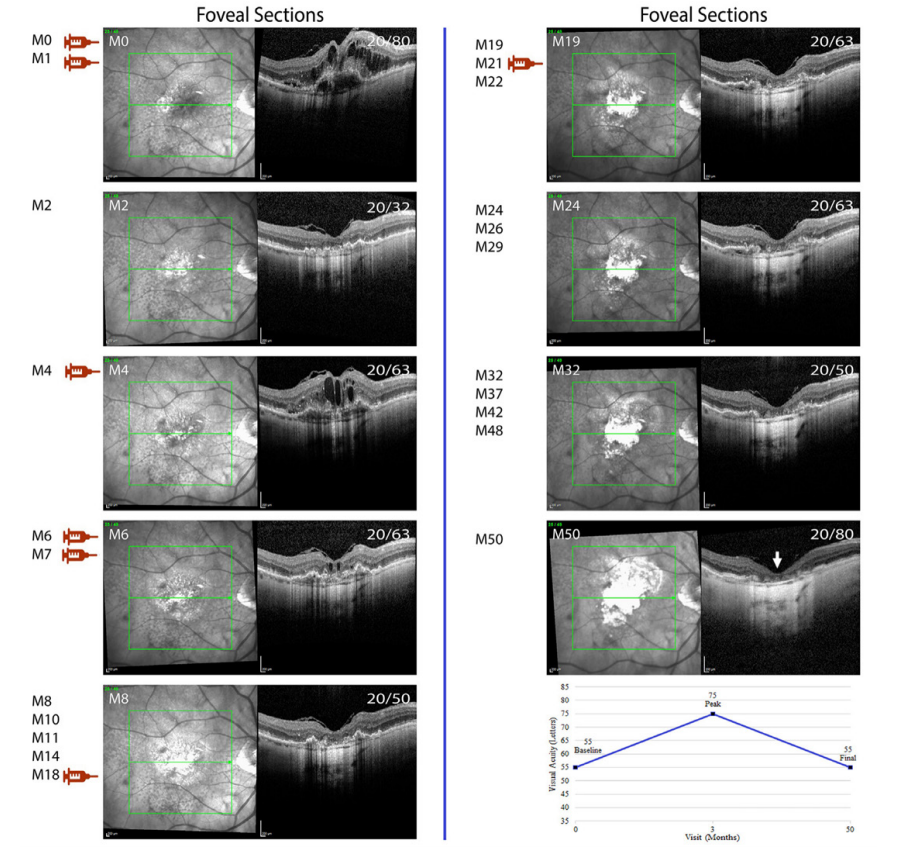

图 2 抗VEGF治疗期间血管性色素上皮脱离消退后萎缩的快速发展

Figure 2 Rapid development of atrophy after collapse of a vascularized pigment epithelial detachment during anti-VEGF treatment

第一、二列分别显示43号受试者第23和15断面的IR图像及SD-OCT图像。左上角表示随访时间(单位:月),右上角表示Snellen视力值,注射符号(蓝色:雷珠单抗;红色:阿柏西普)表示抗VEGF药物注射时间点,折线图显示基线视力、最佳视力及最终视力的字母数。

First and second columns show IR images and horizontal SD-OCT scans through sections 23 and 15 respectively from subject 43. Top left corner shows follow-up visits in months (M) and top right corner shows Snellen visual acuity. Injection symbols (blue: ranibizumab, red: aflibercept) show the visits at which anti-VEGF injection was administered. Line graph shows baseline, peak and final visual acuity in letters.